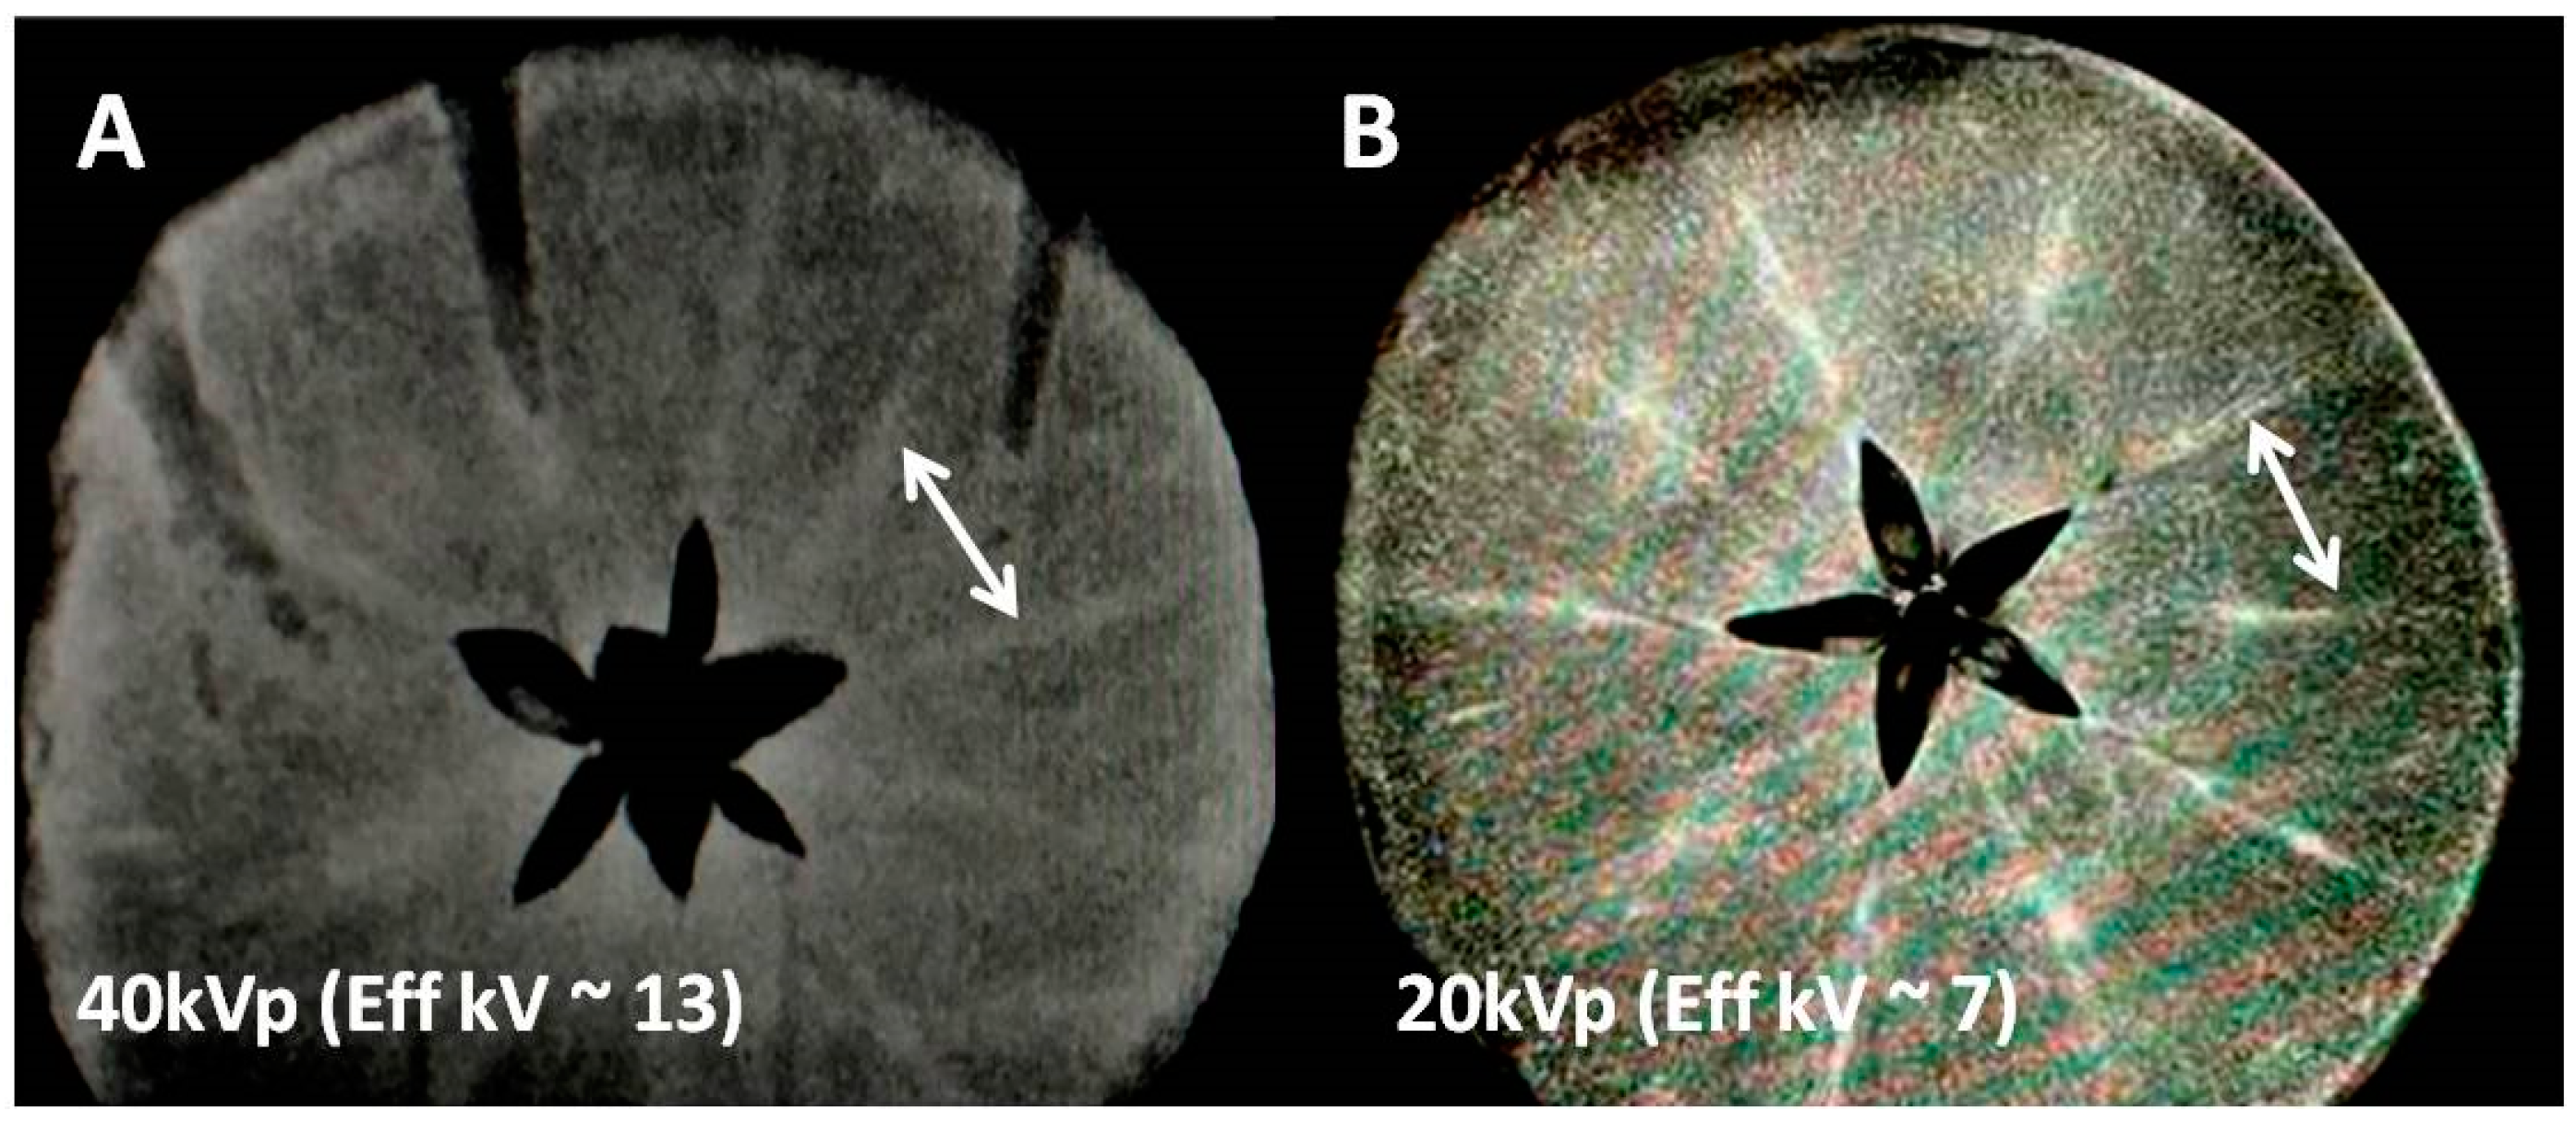

For two tissue regions (consisting of two different elements) low energy X-ray absorption in each tissue is dominated by photoelectric effects and depends on the fourth power of the tissue atomic number (Z4) i.e., X-ray absorption is greater for the heavy atoms. This factor theoretically can create an inherent tissue contrast spanning several orders of magnitude (64 using in vivo tissue effective Z of 6 and 534 for iodine with Z = 53). However, creating differential X-ray absorption within the same tissue for light weight minerals (e.g., iron, calcium, magnesium, potassium etc.) can be substantially difficult due to the volume averaging of minute amounts of such metal ions in normal tissue. In our experiment design we kept the X-ray peak energy low, 40/20 kVp (Figure 1) 44 kVp (Figure 2), respectively. This allowed the mean energy range to be just above the K and L edges of transition metals but still far above the most abundant alkaline metals. Hence, as verified by MR images we are able to favor detection of the Fe and Mn rich tracks by MRI (Figure 1), while arguably discriminating alkali and alkaline earth elements with mean X-ray energies (15 and 7 keV) far above the alkali elemental k edges (approximately 2–3 keV) in Figure 1 and Figure 2. We explored the detectability limits of clinical X-ray systems for endogenous biometals that are lightweight and less abundant and hence hard to detect for the above reasons.

Figure 1.

X-ray images of the mineral-rich apple at two different X-ray energies showing mineral conspicuity as a function of mean X-ray energy. (A) Non-contrast X-ray image at 40 kVp/10 mAs (with mean energy approx. 13 keV) using a clinical scanner; two typical high attenuation tracks marked by a white arrow indicate either K or Fe concentrated regions (Table 1). (B) Another apple slice showing the same mineral tracks at higher mineral conspicuity presumably due to lower kVp (soft) mammographic X-ray beam (20 kVp/10 mAs with mean energy approx 7 keV, close to k-edges of transition metal ions but far from k-edge of K ions, Table 1).

The current work barely touches upon the detection limits and does not set the goal for residual Gd detection for the purpose of neuro or nephro toxicity. Our work uses paramagnetic sensitivity advantages to detect only Mn and Fe that has significant implications in enzyme and carbohydrate homeostasis. It seems that the endogenous imaging detection of most of the minerals in native fruits is substantially difficult for clinical MR scanners that are basically vastly abundant proton imagers, while microscopic amounts of minerals are often homogenously distributed at ppm concentrations. Apple seems to be a small exception and has been used to demonstrate the advantages of chelation and transmetallation. It has mineral tracks probably at higher concentrations than the average reported in Table 1. Iodinated and gadolinium complexes are capable of causing the accumulation of paramagnetic or lanthanide elements extracted from the bio environments in both fruits and offer a detectable MRI signal (see both wells in Figure 4 and second wells in Figure 2 for both apple and sweet potato: with only iodinated exogenous input). Since iodine is not MR active, we believe this is due to the accumulation of native Fe or Mn at the iodine sites. This may mean that chelation has created a higher concentration of Fe or Mn and now MR is sensitively detecting those. This is also favoring track detection in apples in Figure 1 where low kVp (20 kVp, mean energy approximately 7 keV) in the mammographic system provides a more favorable K-edge detection for Fe in apple as compared to 40 kVp (mean energy approximately 13 keV).